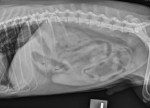

Ventrodorsale